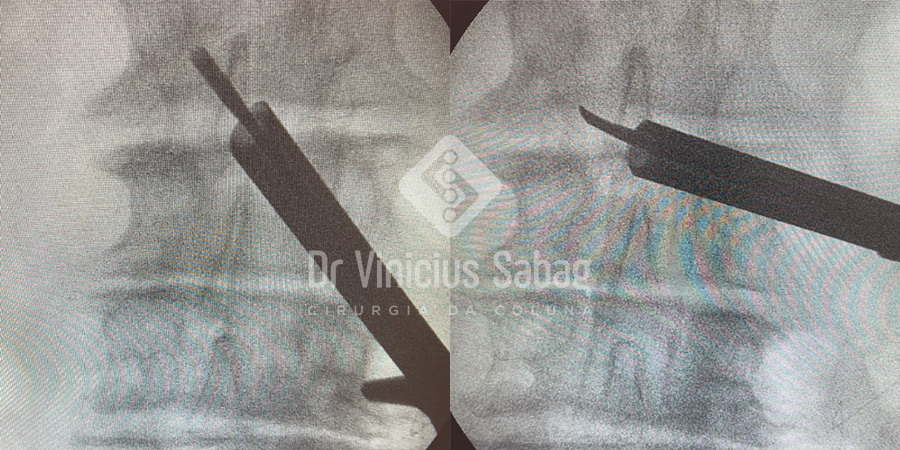

No entanto, optamos por uma abordagem minimamente invasiva, técnica que permite a descompressão dos nervos por incisões de aproximadamente 1 cm, sem necessidade de fixação com parafusos, com menor risco de complicações e alta hospitalar no mesmo dia, com o paciente andando.

A cirurgia foi realizada por meio de duas pequenas incisões, pelas quais foi possível descomprimir todos os níveis comprometidos.

Radiografias intraoperatórias utilizadas para auxiliar na descompressão completa dos nervos.